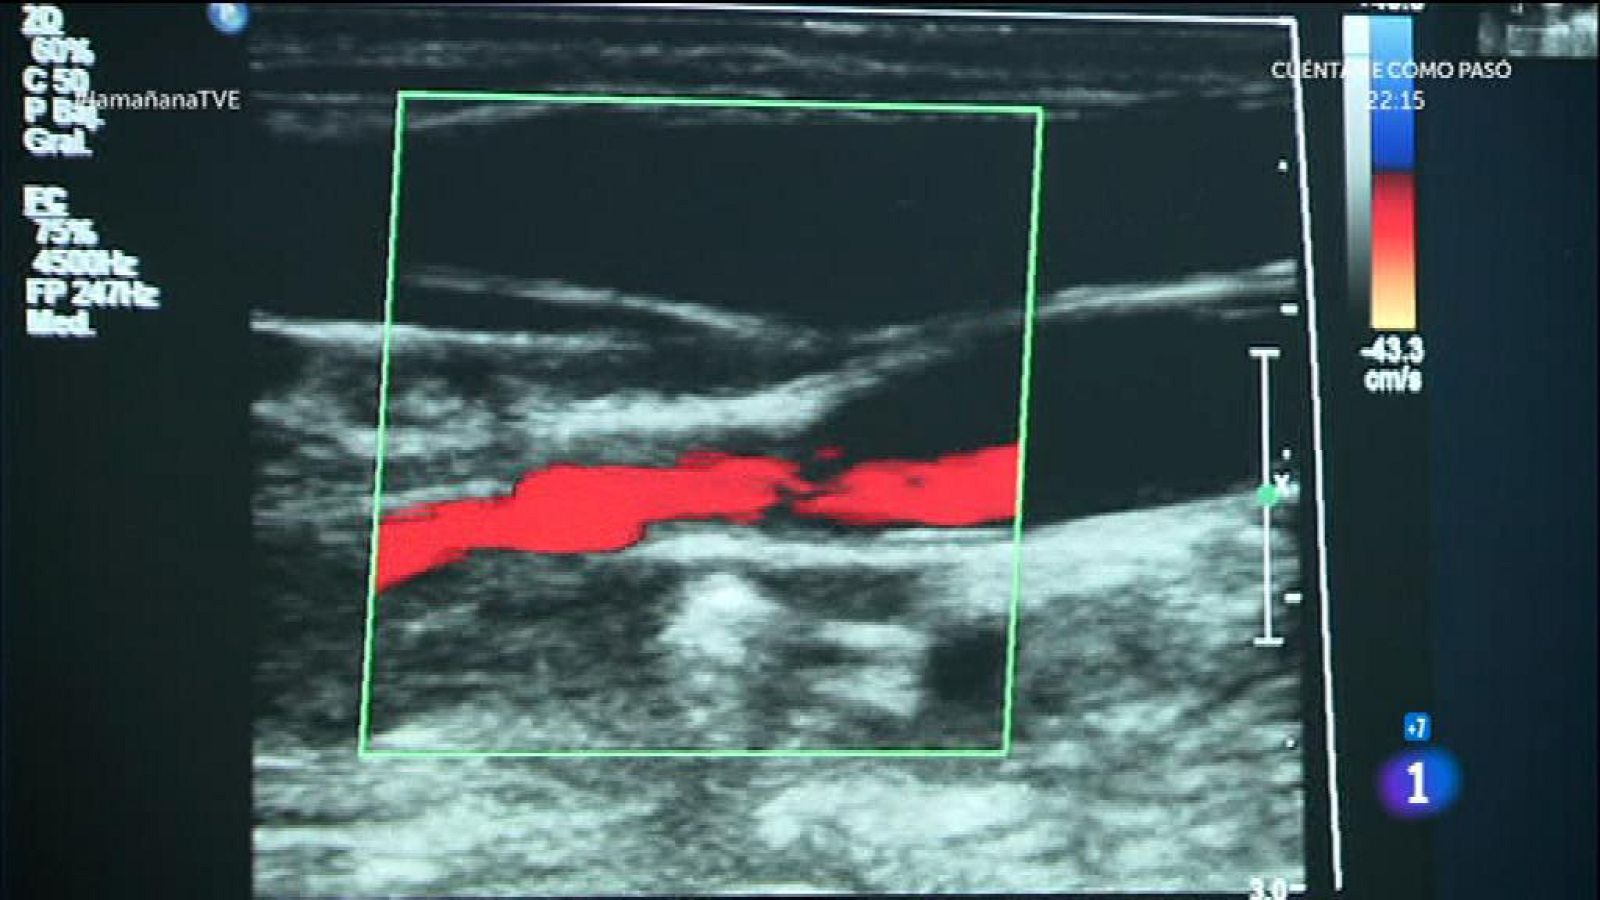

Lesión cerebral evitable

Lesión cerebral evitable